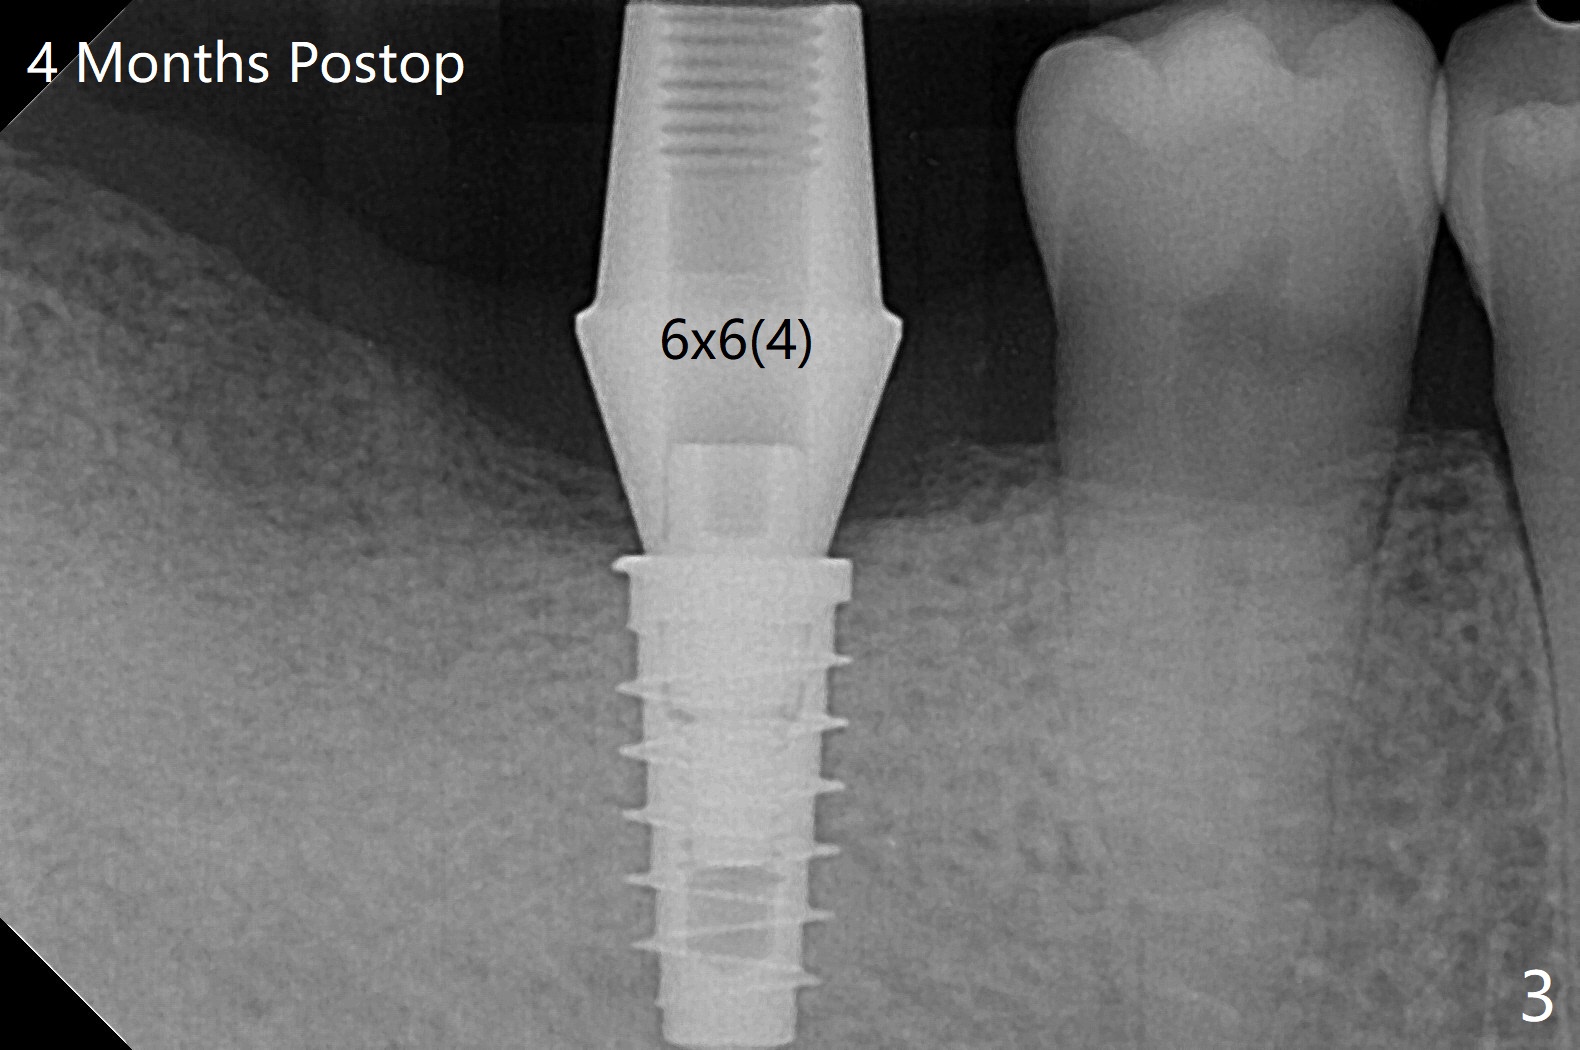

右下7(以前近中倾斜移位)位点保留后13月回来做6导板种植,骨质密度高,钻洞慢,注意灌溉制冷,使用4.5毫米功螺纹钻头后,植入4.5x9毫米植体(图一:牙槽嵴下~1毫米,扭力大约35Ncm)。使用5.5和6.0毫米profile drills后,放置6x3毫米愈合基台,最后植体,基台周围放置自体骨(事先翻瓣)。看样子邻牙植骨(图一:白线)对植牙有帮助。翻瓣缺点是缝合后伤口保护,牙周敷料术后一两天脱落(远中植体最好使用修复基台,不容易脱落),造成病人恐慌,第二次敷料术后第七天脱落,可欣的是伤口术后第八天愈合(图二)。术后四个月更换基台(图三),调整高度后,取模。由于基台边缘龈上,先拧紧(30 Ncm)后粘固,之后不再取出基台。然后对合取模,修改对合牙冠。